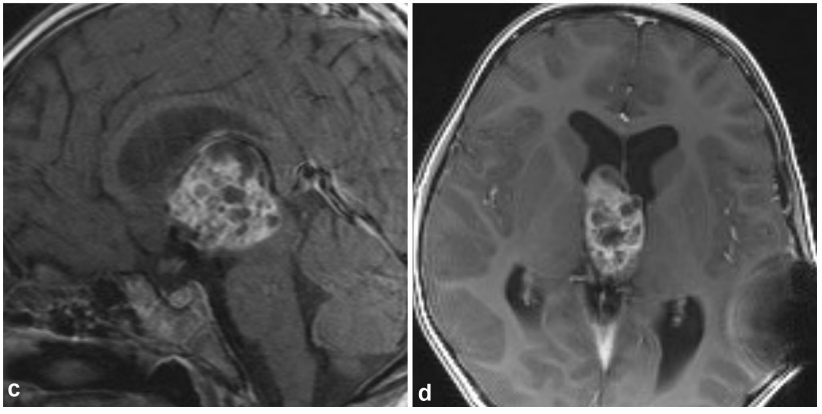

眼看着孩子精神越来越萎靡,小天的父母再次带孩子四处求医。很快,一名儿科医生发觉小天的头围偏大,进一步检查发现脑室扩大及脑积水。随后MRI扫描发现,小天的脑部松果体区生出了一个“怪瘤”,正是畸胎瘤。

手术从后枕骨开颅,经小脑幕进入松果体(Occipital transtentorial Approach),其难度不言而喻。最终鲁特卡教授对肿瘤实施了最大程度切除。当教授通知他们手术很成功时,小天父母喜极而泣。

颅内畸胎瘤是颅内生殖细胞瘤中的一种亚型,是由一个以上胚叶多种组织构成的一种先天性肿瘤,常见于松果体区或第三、四脑室。

畸胎瘤易导致脑脊液循环通路梗阻,进而引起脑积水。多数患儿以颅内压增高为首发症状,表现为头痛、恶心、呕吐,眼科检查可见双侧视乳头水肿。

畸胎瘤的影像学特征有显著特点,颅脑X线平片多数显示有颅内压增高征象,如发现有牙齿、小骨块、钙化影像,则更有助于定性诊断。此外,胎儿的畸胎瘤一般可以在孕20-24周的产检中发现,通常为良性。